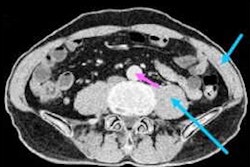

Taking a different approach for improving detection of lung nodules, the researchers sought to develop a deep-learning method that can also analyze the sinogram data. To develop their algorithm, they selected 4,804 juxta-pleural nodules from 200 patients who were included in the Lung Image Database Consortium and the Image Database Resource Initiative dataset. These nodules are close or attached to the chest wall and are relatively small in size. Their texture also appears similar on the images to the surrounding environment; consequently, they are challenging to detect, Gao said.

In their study, the researchers first extracted suspicious nodule candidates from the CT images using their previously developed vector quantization technique. After the nodule candidate was projected to the sinogram domain, the researchers then applied the deep-learning model on the sinogram data to reduce false-positive results.